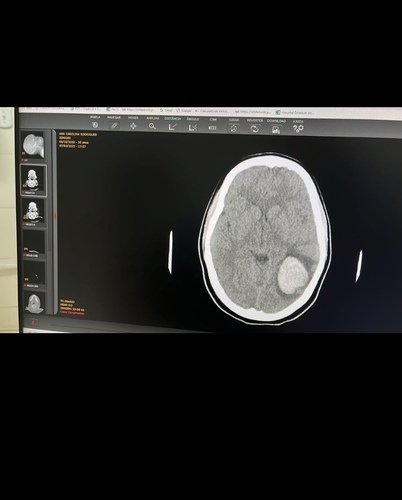

Olá, nos familiares e amigos da Ana Carolina Rodrigues Simioni fizemos essa vaquinha com o propósito de arrecadar 50.000,00$ para sua cirurgia de extrema urgência no Hospital São Silvestre em Aparecida de Goiânia. Ana Carolina tem apenas 20 anos, uma menina meiga e cheia de sonhos, ela descobriu um aneurisma cerebral que começou uma hemorragia interna e seu quadro médico está gravíssimo, correndo risco de vida. Temos muita fé que com a ajuda de todos ela vai conseguir se curar. Obrigada a todos de coração, Deus abençoe vocês!!